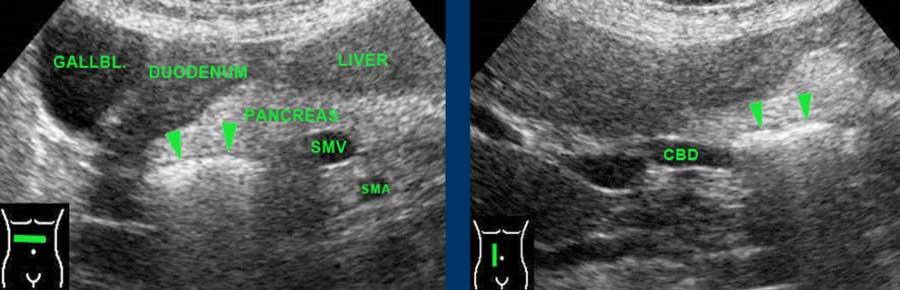

Tá tràng đoạn xuống và đoạn nằm ngang hiếm khi có thể tiếp cận được bằng siêu âm.

Khi được tìm kiếm cụ thể, có thể xác định được các túi thừa tá tràng chứa đầy khí kích thước lớn, hiện diện ở 10-15% dân số bình thường.

Chúng biểu hiện dưới dạng một phản xạ (đường cong) tuyến tính trong đầu tụy.

Lưu ý rằng những bệnh nhân này thường có ống mật chủ rộng hơn so với bệnh nhân bình thường.